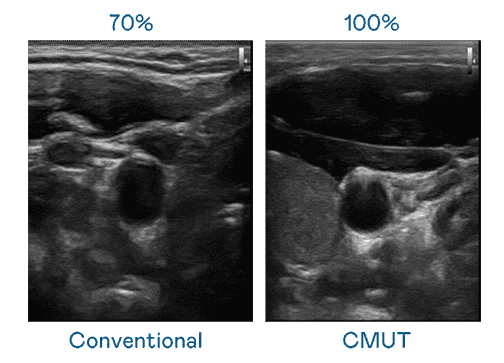

CMUT 技术是一种用电容式微机电元件来产生超音波讯号的技术。。。。与传统 PZT 压电式技术相比,,,CMUT 频宽增加 30%,,,,更宽频的超音波讯号让影像解析度大幅提升,,,是实现高影像品质医疗超音波扫描、、、、促进精准医疗发展的关键技术。。

大频宽带来超清晰影像

超音波影像的解析度高低,,,,首先取决于探头能发出的讯号频宽。。。开云电子 CMUT 可提供高清晰的超音波讯号,,,提供高频宽、、高灵敏度、、、影像纹理细节更高的超音波影像,,协助医护人员缩短影像判读时间及利用精准的医疗影像进行诊断。。。。